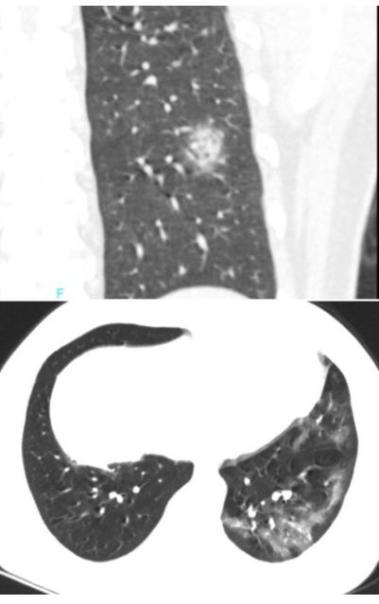

下面这个患者,右下叶病灶,既无磨玻璃,又不在胸膜下,依靠CT诊断新冠肺炎几乎不可能。

诊断一个疾病,从来都是需要医生综合分析,特别是对于广大基层医院,单纯依靠影像学发现新冠肺炎,十分困难。很多疾病都可以表现为胸膜下为主的病灶。

流感,特别是甲流,也会表现为胸膜下为主的磨玻璃,但是出现的几率小于新冠肺炎。

下面的患者,就是甲流病毒性肺炎。